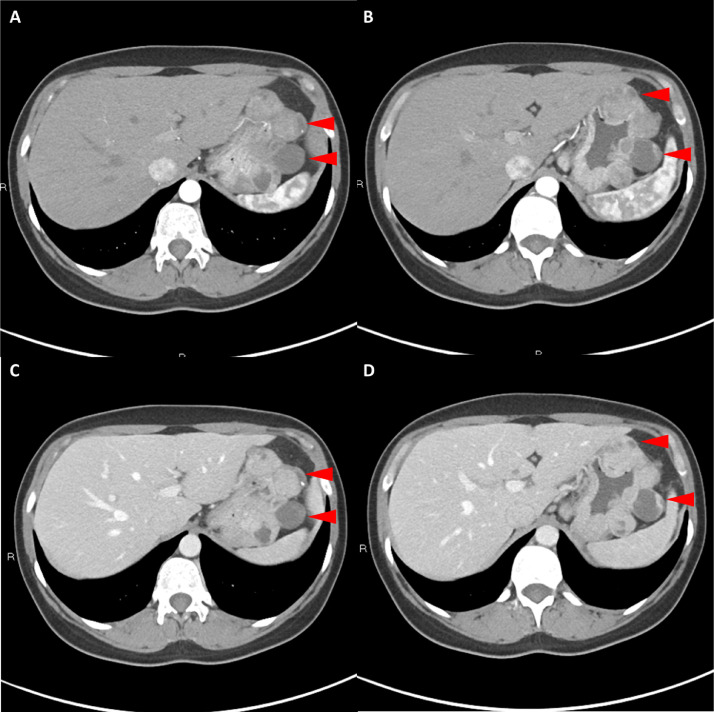

胸部、腹部和骨盆的对比增强动脉和静脉期 CT 显示多个圆形、主要是血管丰富的异质肿块,具有囊性和实性成分,起源于胃底和胃体(图 2-4)。 病变部分呈外生结构,被认为位于粘膜下层。 在颈部多发同步性副神经节瘤的情况下,贼初的鉴别诊断包括多发性副神经节瘤、多发性 GIST 以及转移性疾病。